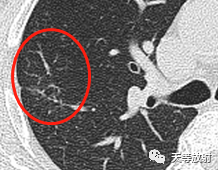

569d828a05faf789b1ebd453727644ef.png

实性为主结节,长条状影。

这个层面出现囊腔+实性结节,囊壁较厚。